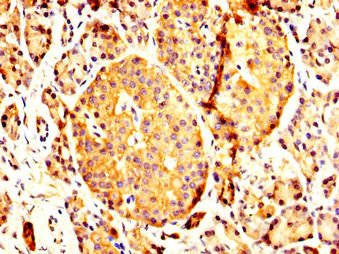

IHC image of CSB-PA017618LA01HU diluted at 1:200 and staining in paraffin-embedded human pancreatic tissue performed on a Leica BondTM system. After dewaxing and hydration, antigen retrieval was mediated by high pressure in a citrate buffer (pH 6.0). Section was blocked with 10% normal goat serum 30min at RT. Then primary antibody (1% BSA) was incubated at 4°C overnight. The primary is detected by a biotinylated secondary antibody and visualized using an HRP conjugated SP system.